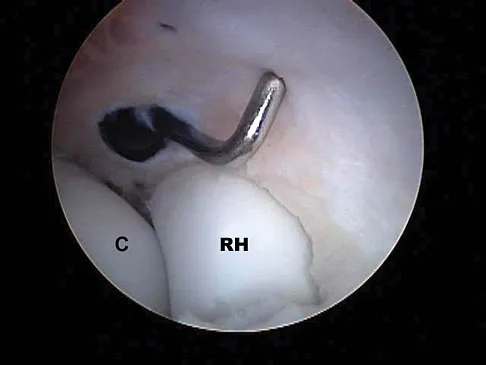

A football player sustains a traumatic anterior inferior dislocation of the shoulder in the last game of the season. It is reduced 20 minutes later in the locker room. The patient is neurologically intact and has regained motion. If the patient undergoes arthroscopic evaluation, what finding is seen most consistently?